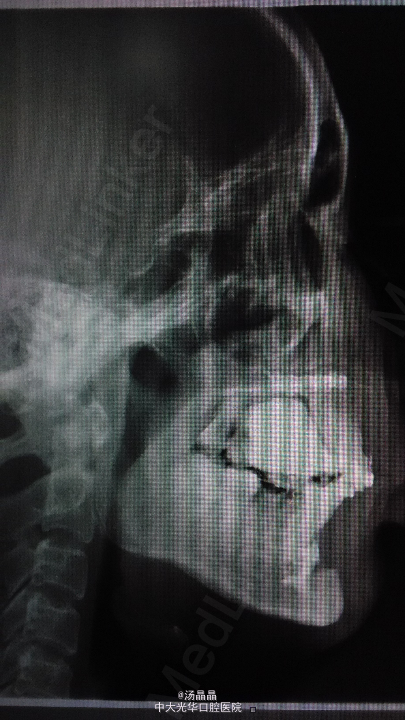

患者,女,30岁,发现双颌前突20余年

面上中下三分之一比例协调,侧面观可见上下唇前突,双侧颞下颌关节运动无明显异常,开口度4厘米,口内检查可见上下颌全口正畸弓丝及托槽,18,28,48阻生,46缺失

诊断为双颌前突,全麻下行双侧上下颌前牙根尖下截骨后退术,双侧上下颌骨部分切除术,上下颌骨内坚固内固定术,14,24,34,44复杂牙拔除术,植入Martin钛板4块,钛钉16颗固定